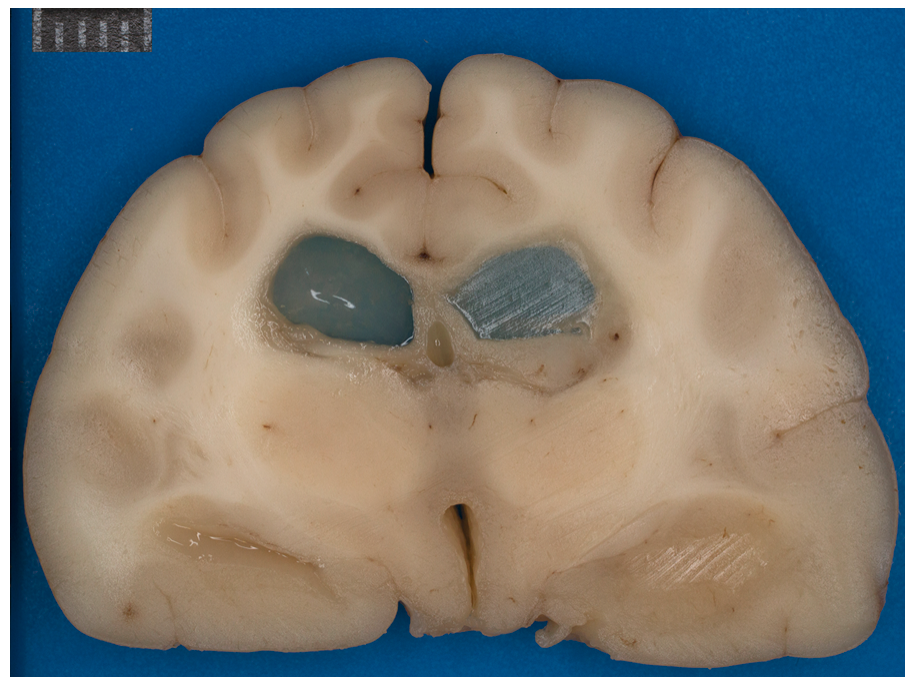

Transverse sections of the brain of a 5-year-old golden retriever showing a dilated left lateral ventricle caused by a choroid plexus papilloma obstructing the left interventricular foramen.